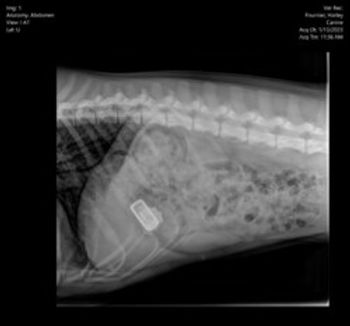

Surgery to remove Fitbit also brought attention to a large rock in the intestine that may have caused further damage if left unchecked